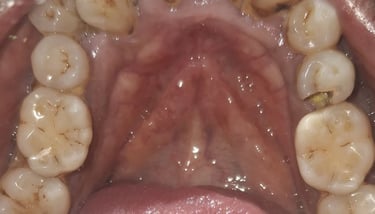

Clinical pictures of teeth requiring RCT

All images are of real cases of teeth where Root canal treatment was performed to remove infection and preserve the natural tooth restoring normal chewing and function of teeth.